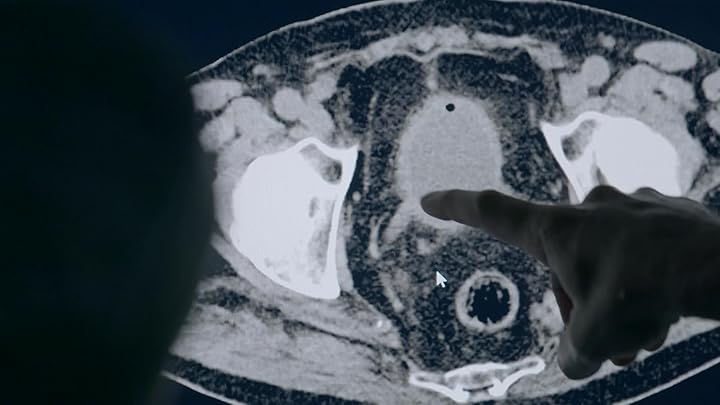

Surgeons at University Hospital Southampton take on a high risk surgery to try and remove a life threatening tumour.

Surgeons at University Hospital Southampton perform intense and complex procedures to save patients' lives. In this episode the consultants carry out high risk spinal surgery and attempt to repair a section of the body's biggest blood vessel that's threatening to burst.